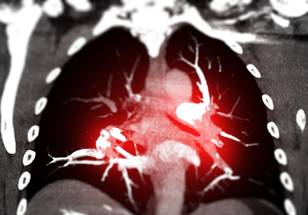

Almodóvar said those comorbidities include neurological and metabolic disorders, liver and kidney diseases, cancers and cardiovascular diseases. They also include pulmonary hypertension, which is currently the focus of her lab’s research. Pulmonary hypertension is a condition in the lungs caused by severe narrowing of the arteries. It increases the pressure in these arteries and affects the right side of the heart, which is not anatomically equipped to handle such high pressures. If the condition progresses without diagnosis or treatment, the result is often death due to right heart failure.

“The blood vessels in the lungs are severely affected in the presence of HIV, and this leads to serious illnesses in the lungs and heart,” Almodóvar explained. “In this study, we will conduct experiments to understand how HIV molecules change the way that lung molecules interact so that we can propose novel therapies to prevent lung diseases in people with HIV.”